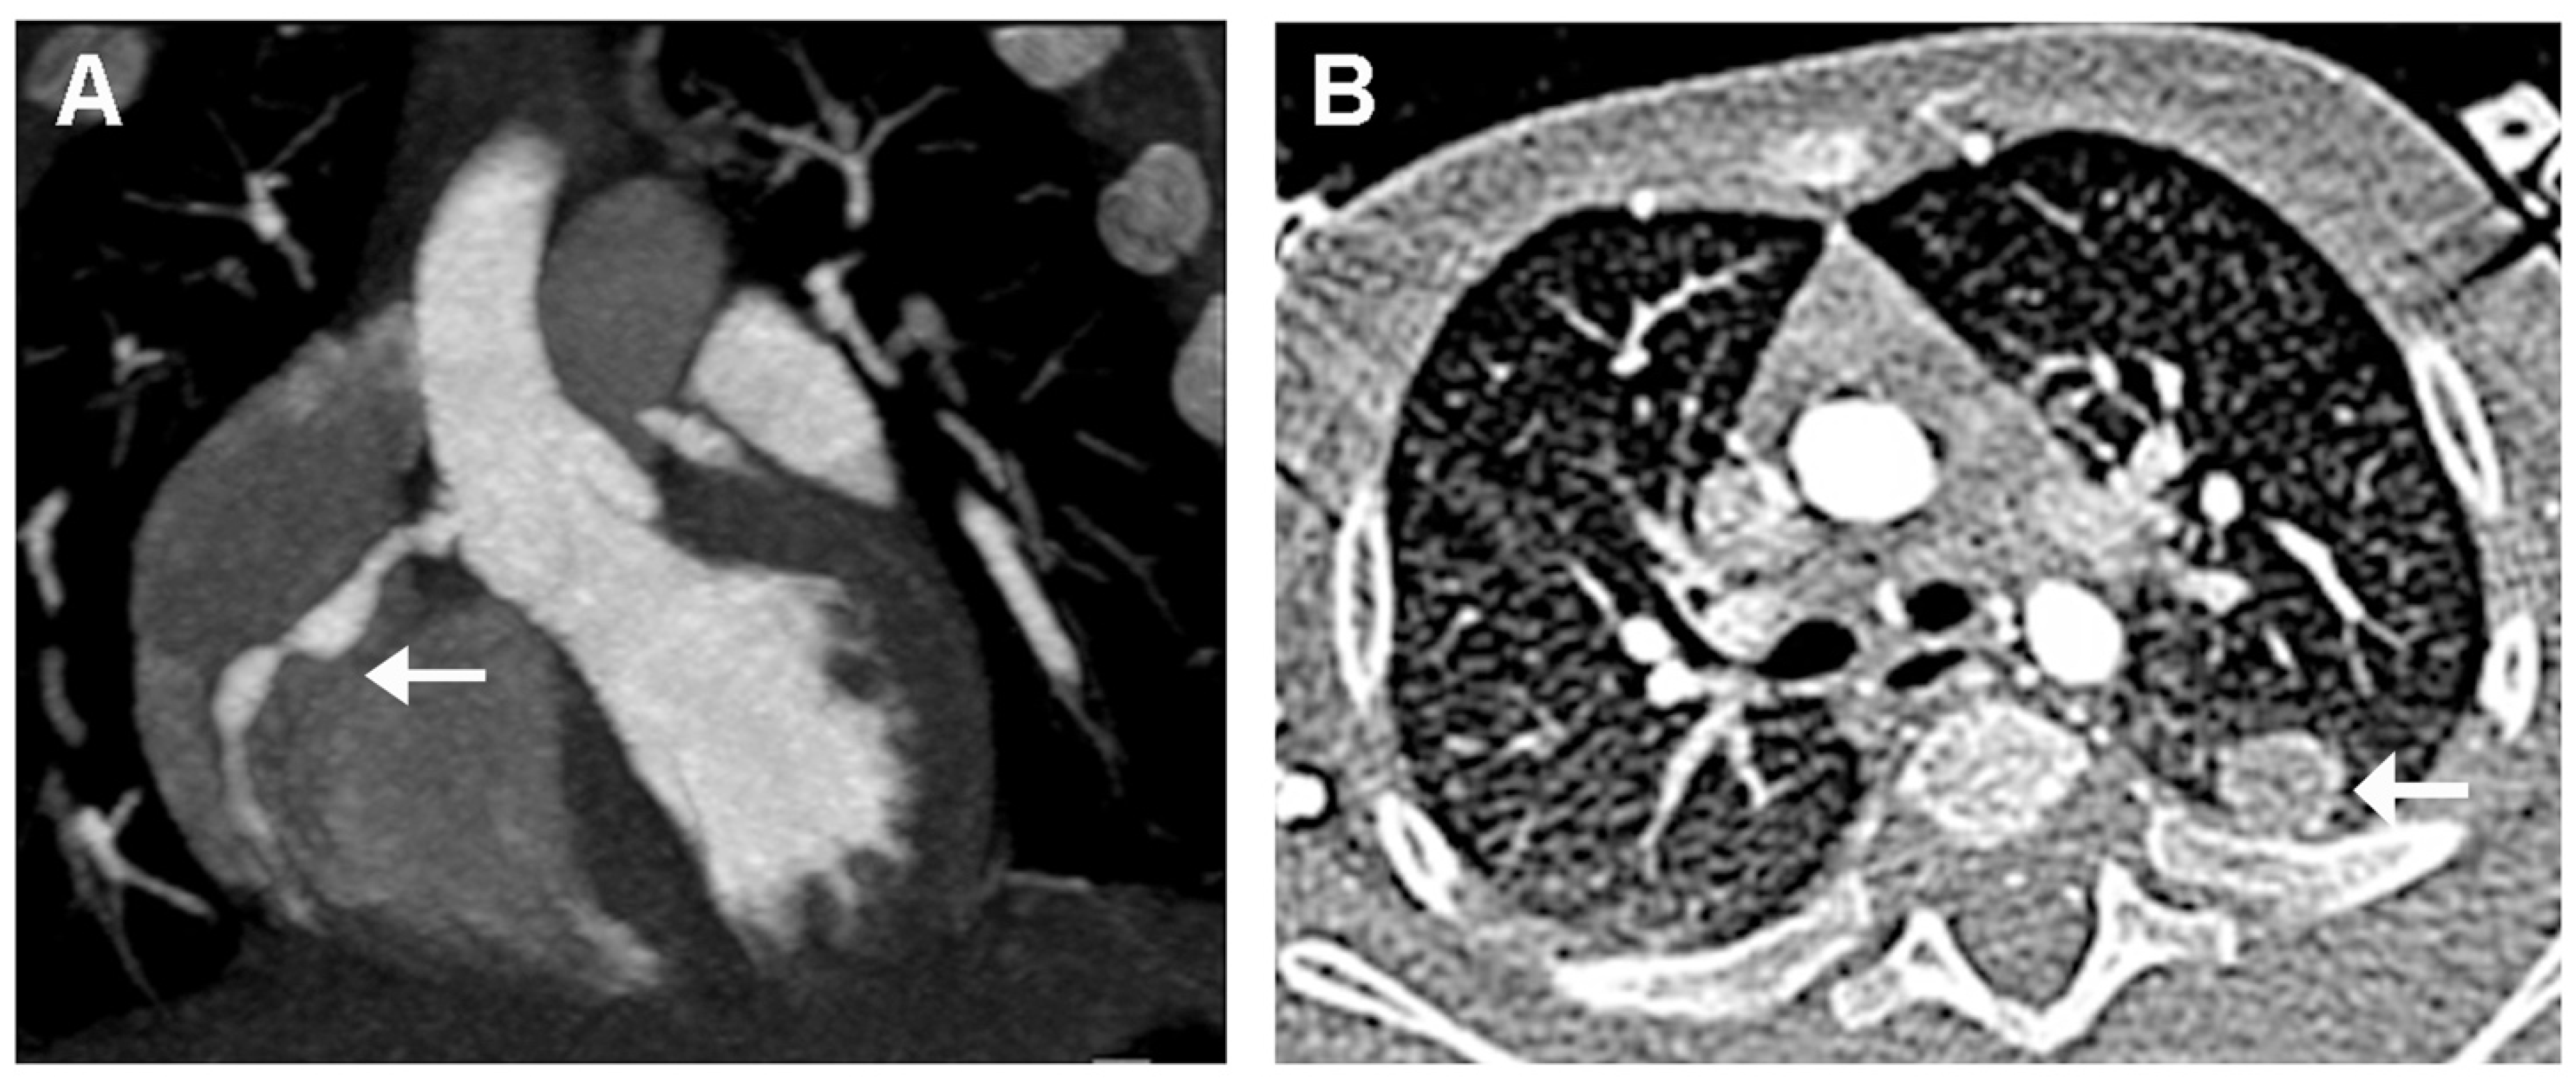

- Song, D.; Liu, X. Kawasaki disease with pulmonary nodules: Two case reports and literature review. Transl. Pediatr. 2021, 10, 1952–1959. [Google Scholar] [CrossRef] [PubMed]

- Freeman, A.F.; Crawford, S.E.; Finn, L.S.; López-Andreu, J.A.; Ferrando-Monleón, S.; Pérez-Tamarit, D.; Cornwall, M.L.; Shulman, S.T.; Rowley, A.H. Inflammatory pulmonary nodules in Kawasaki disease. Pediatr. Pulmonol. 2003, 36, 102–106. [Google Scholar] [CrossRef]